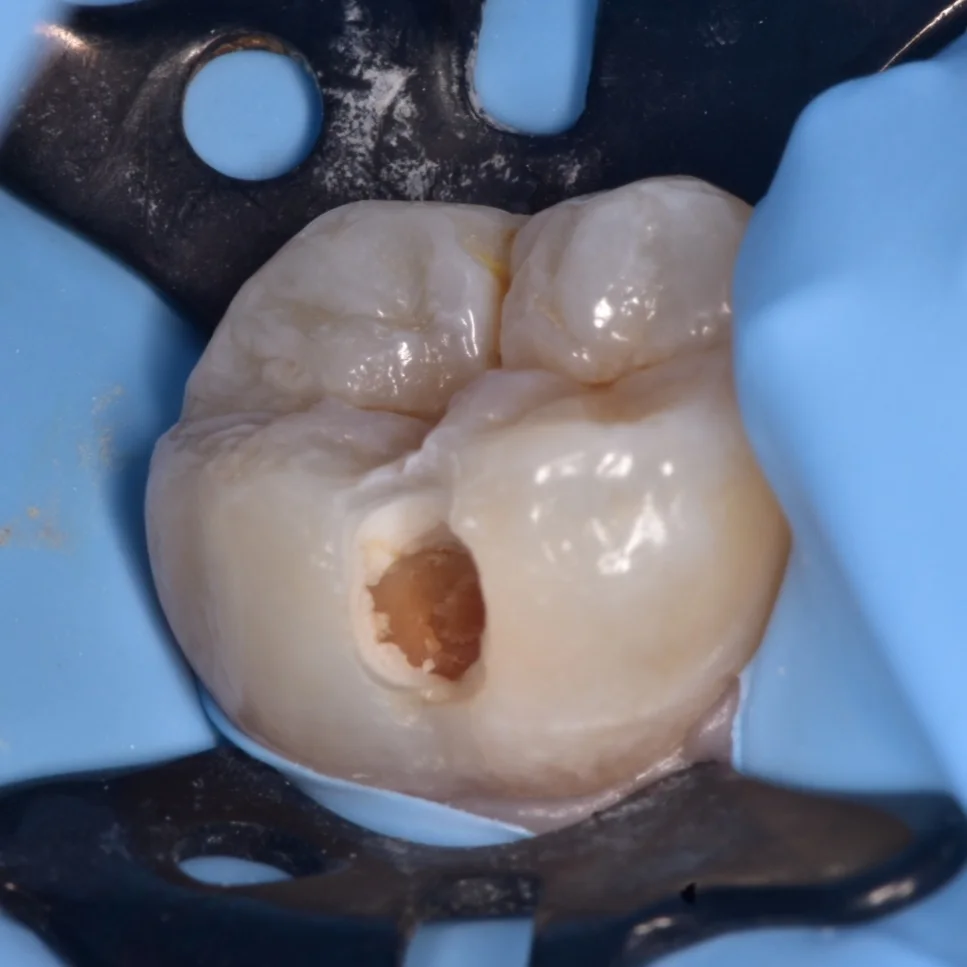

Initial situation showing the buccal carious lesion

During cavity preparation, when you see th white line between the soft caries and dentin or enamel that's mean the caries extend deep

All caries removed, unsupported and irregular enamel removed and the pulp saved